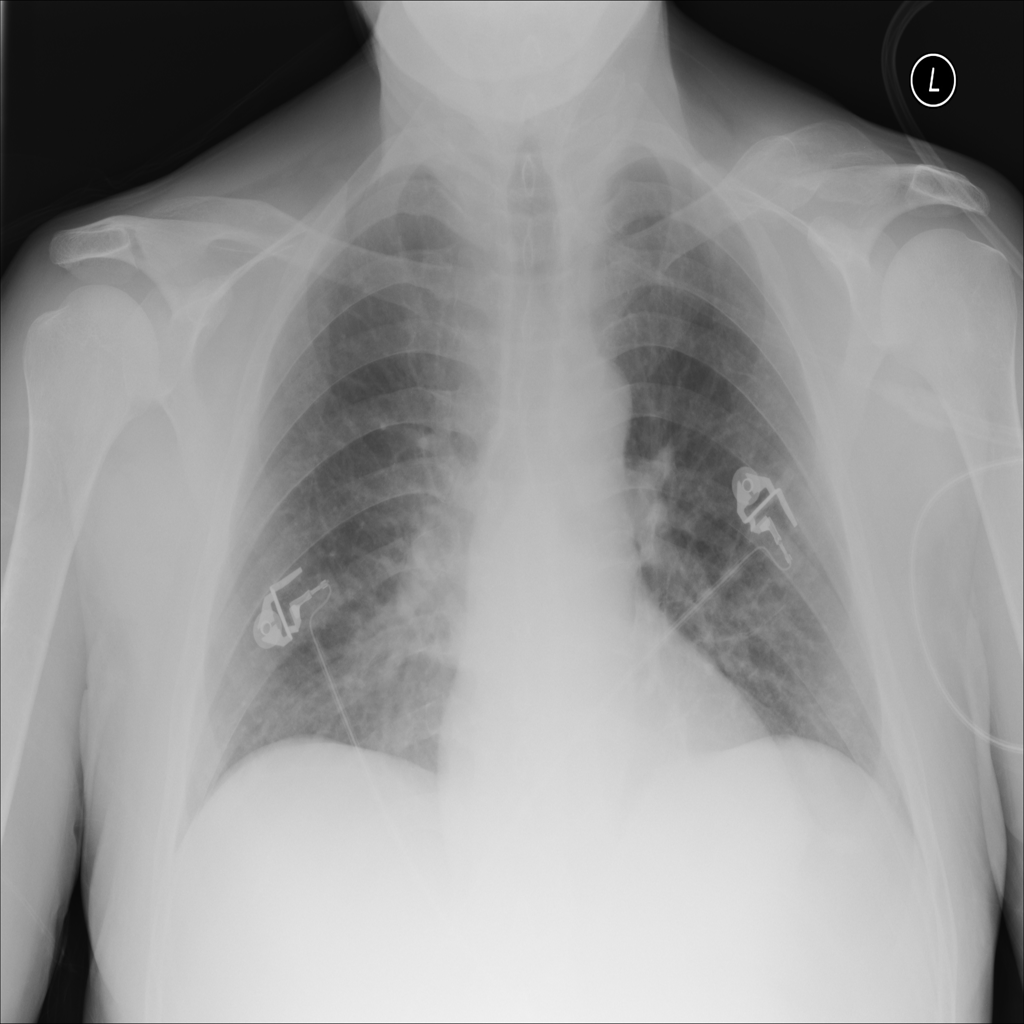

PAT-DB80 · IMG-000Atelectasis

PAT-DB80 · IMG-000

PA